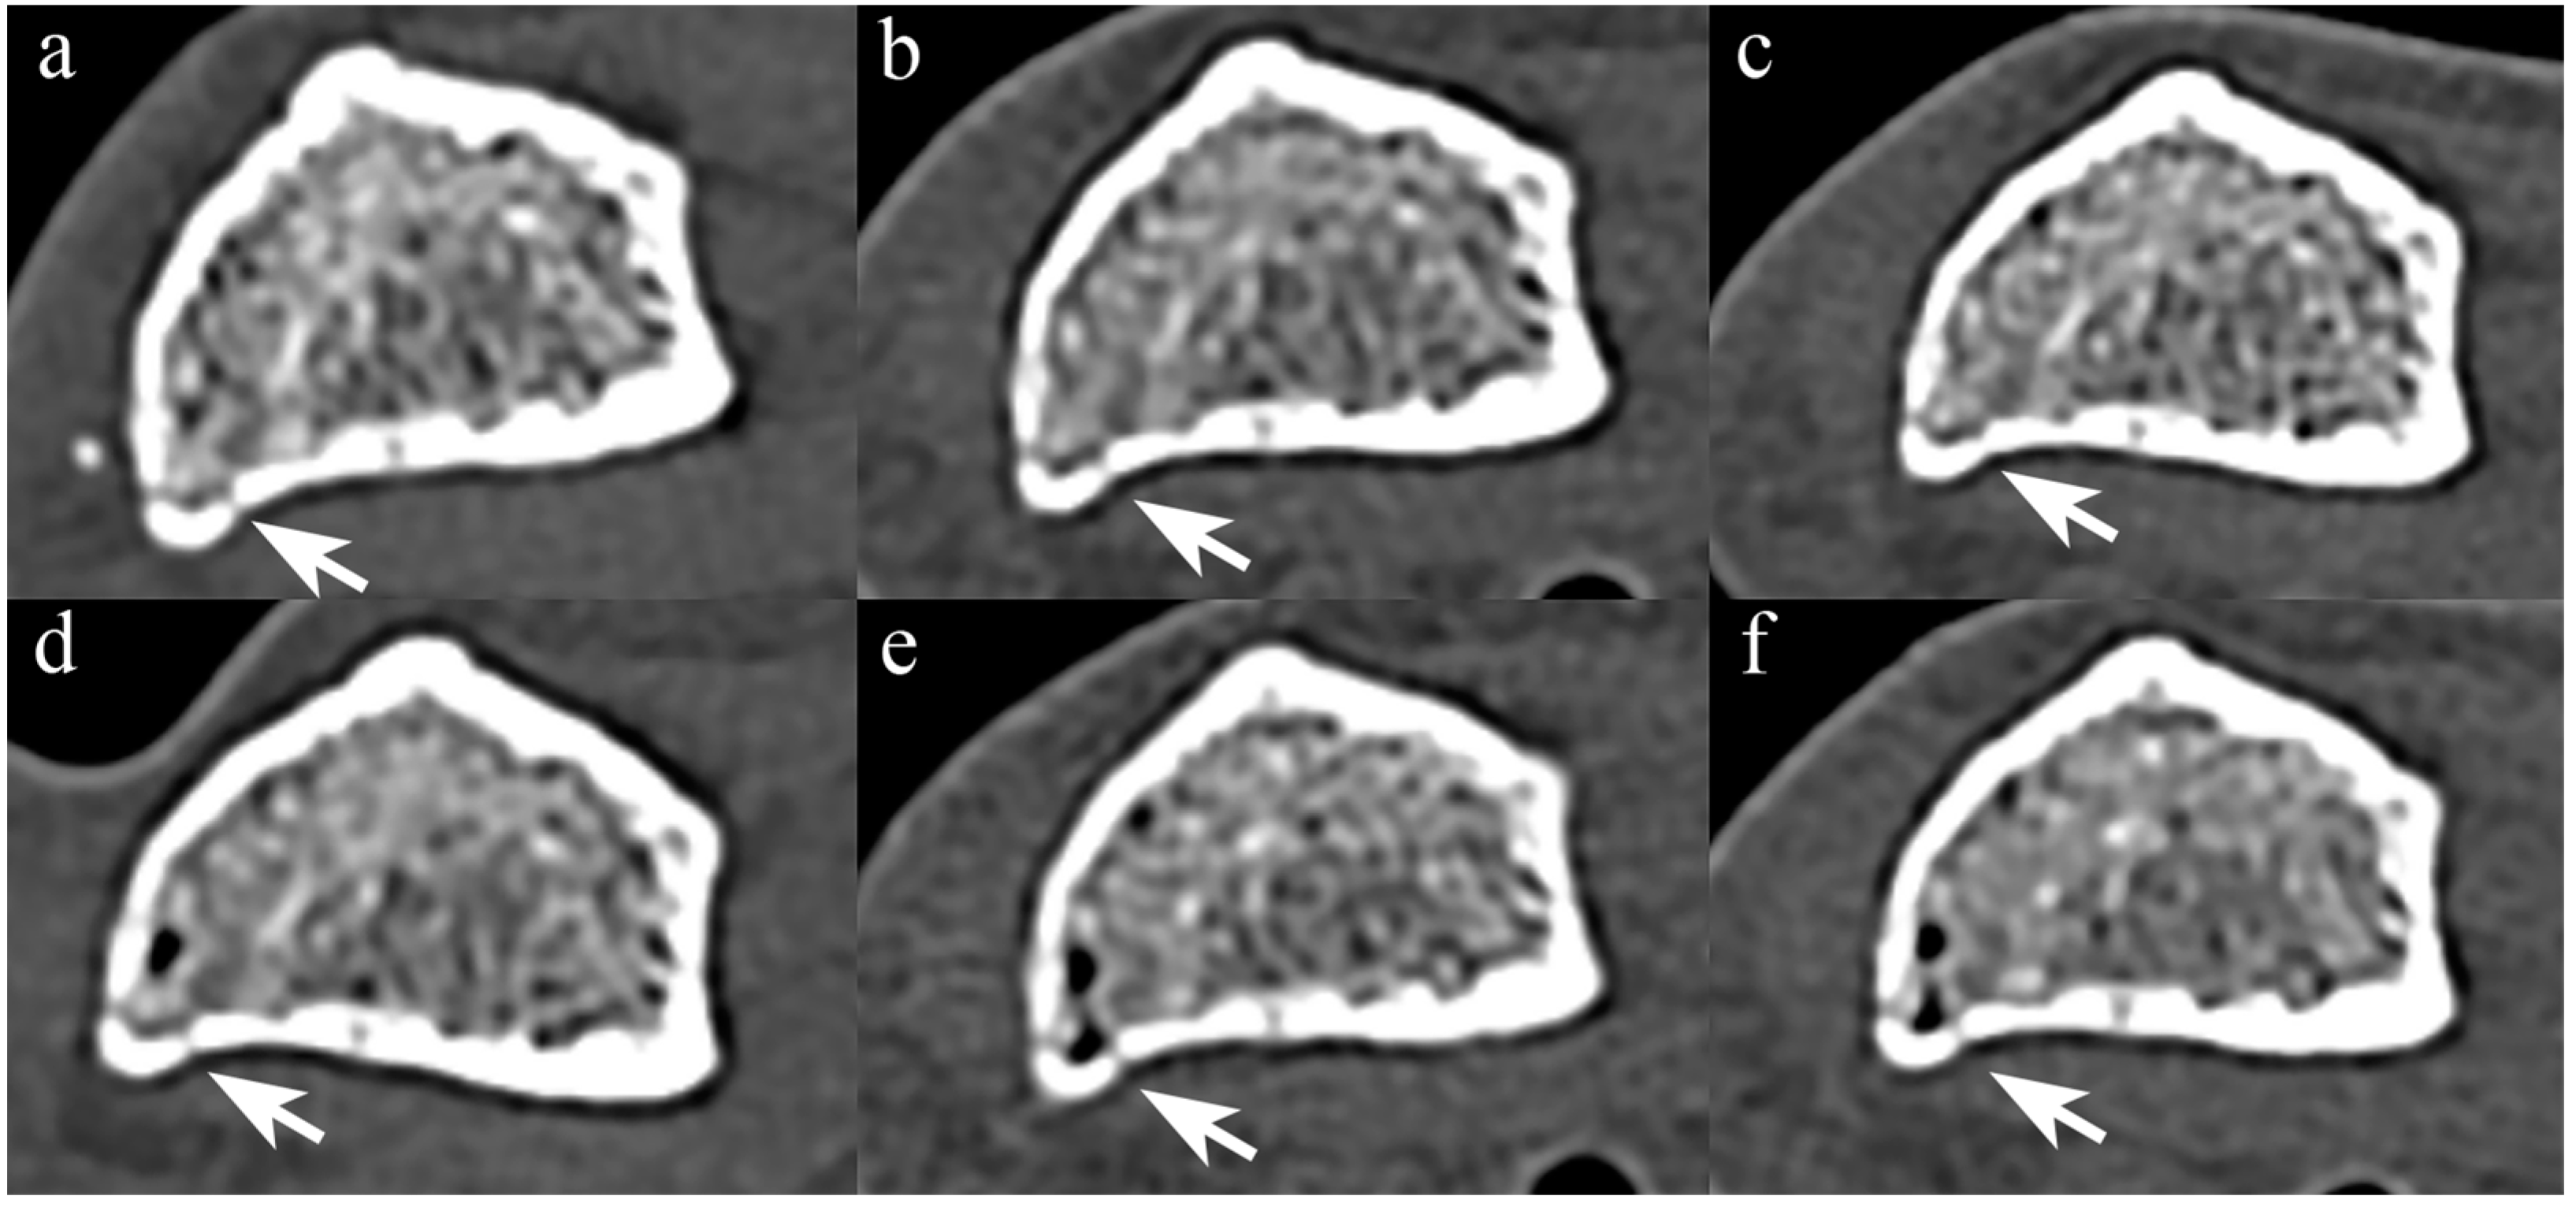

Figure 5 compares Sn−, Sn+, and VMI images from PCCT and two representative EIDCTs (Drive and Force). Images from all scanners are provided in Figure S1.

Figure 5. Comparison of PCCT and two representative dual-energy EIDCT images containing metal artifacts. Images were obtained by using Alpha (panels (ac)), Drive (panels (df)), and Force (panels (gi)) scanners. The left column shows images obtained without tin filtration (Sn−), the middle column shows images obtained with tin filtration (Sn+), and the right column shows 120 keV virtual monoenergetic images (VMIs).

Although there were no significant differences in both subjective scores (overall metal artifacts and adjacent tissue visibility) among Sn− images, overall metal artifact severity in PCCT exhibited a trend toward higher scores than EIDCTs (Table 8). For Sn+ images and VMIs, no statistically significant differences in both subjective scores were observed between PCCT and EIDCTs. Inter-reader agreement among three interpreters was 0.92 (95% CI, 0.79–0.98; p < 0.001) for scores of overall metal artifacts and 0.82 (95% CI, 0.21–0.95, p < 0.001) for adjacent tissue visibility

3.5. Quantitative Results of the Third Session

For PCCT, the areas of streak artifacts significantly decreased in the following order: Sn− > Sn+ > VMI (p < 0.001). The streak artifact areas for PCCT were significantly larger than those for EIDCT, both in Sn− images (p < 0.001) and Sn+ images (p < 0.001). However, the areas of streak artifacts in VMIs generated using PCCT were significantly smaller than those produced using three dual-energy EIDCT scanners (p < 0.001 or 0.001; Figure 6).